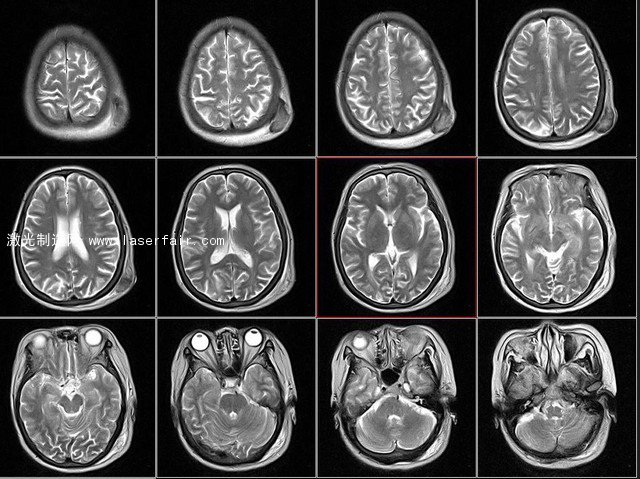

人腦核磁共振切面圖 圖源ququliao.com